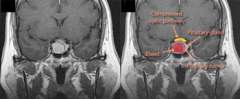

One method doctors use to diagnose pituitary apoplexy is using MRI scans. At the UCLA Pituitary Tumor Program, we use a special MRI pituitary protocol in order to best visualize the tumor. Our specialists examine the scan together to determine the size of the bleed.